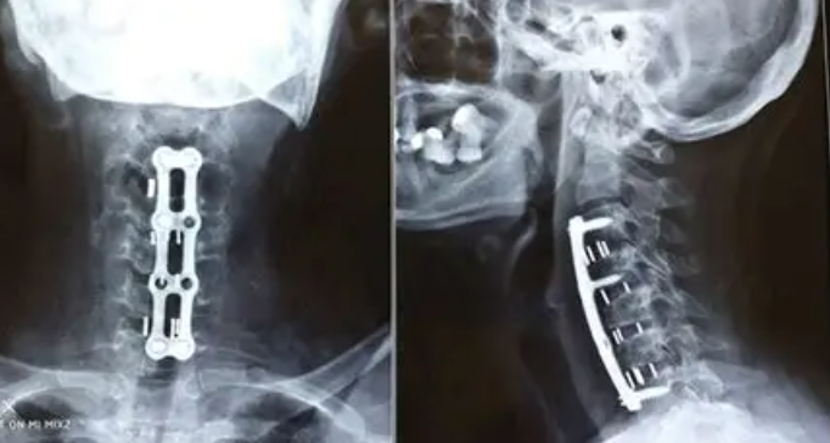

After Surgery Results

ACDF (Fusion)

Anterior Cervical Discectomy and Fusion to remove a damaged disc and fuse vertebrae.

Artificial Disc Replacement

Replaces the damaged disc with an artificial one to maintain motion.